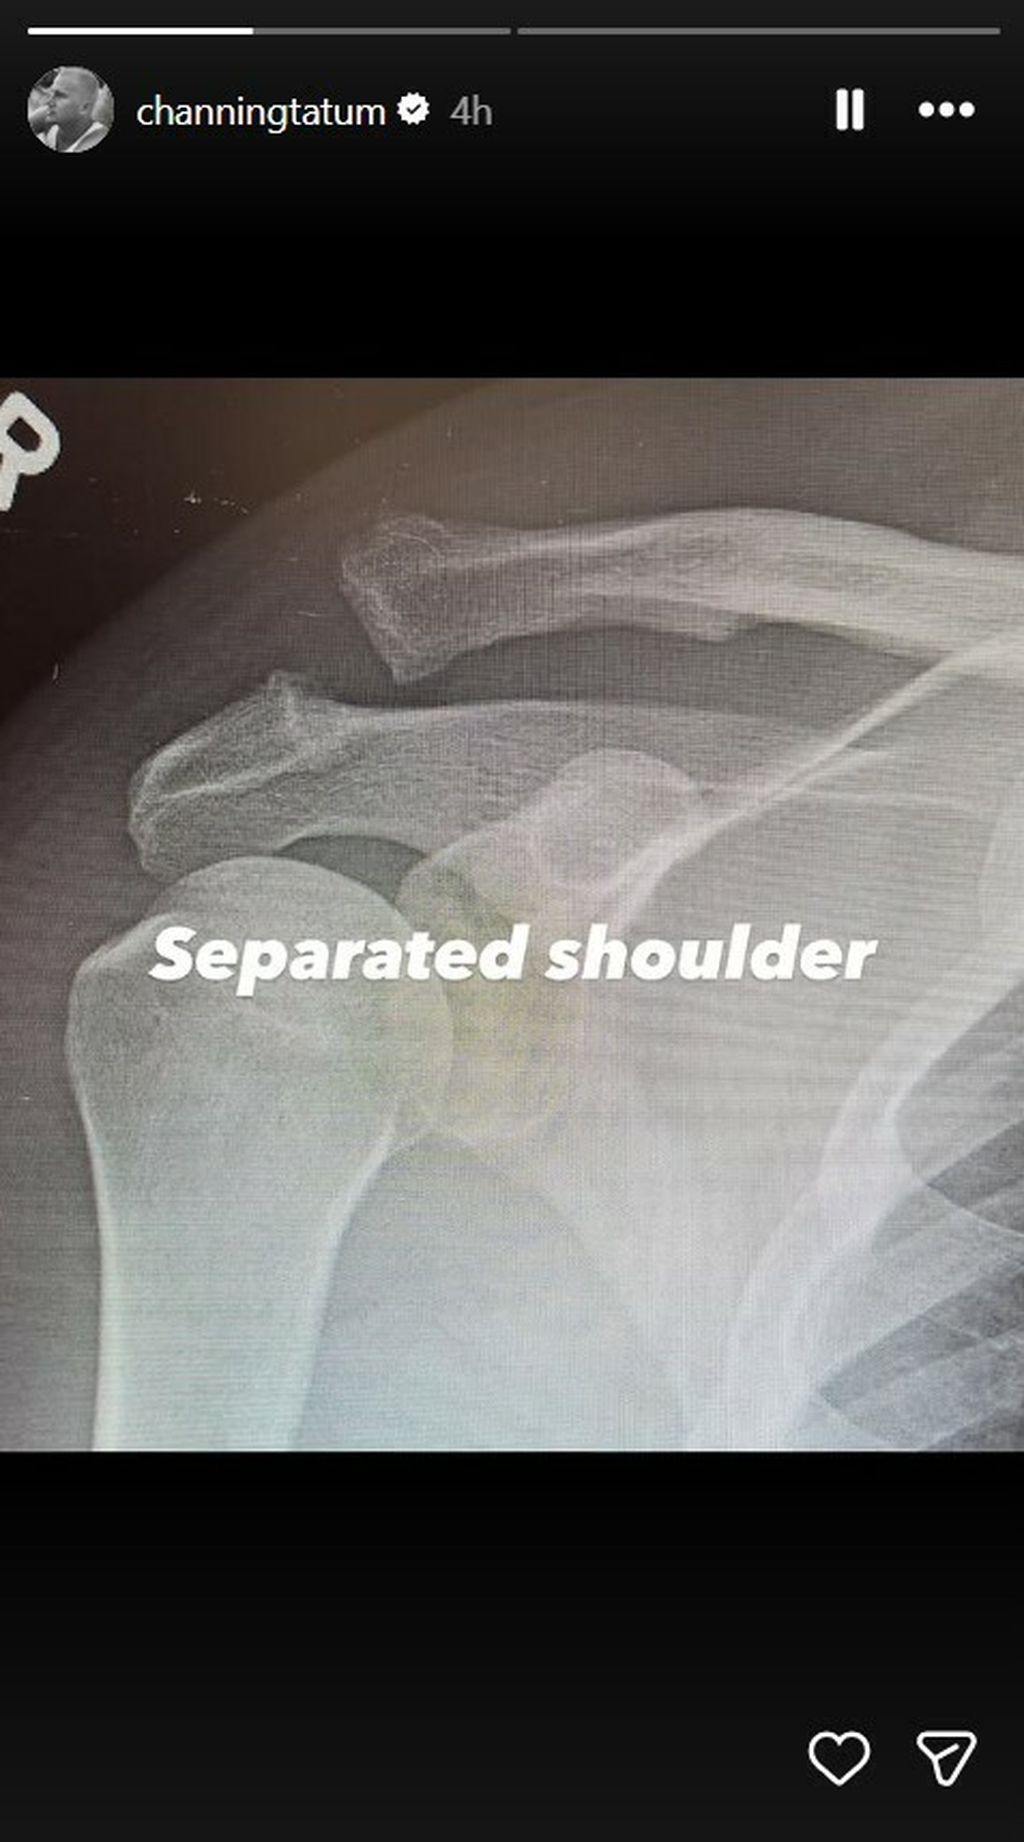

U sljedećim objavama otkrio je i razlog boravka u bolnici podijelivši rendgenske snimke ramena, dao je do znanja da je riječ o ozbiljnoj ozljedi ramena.